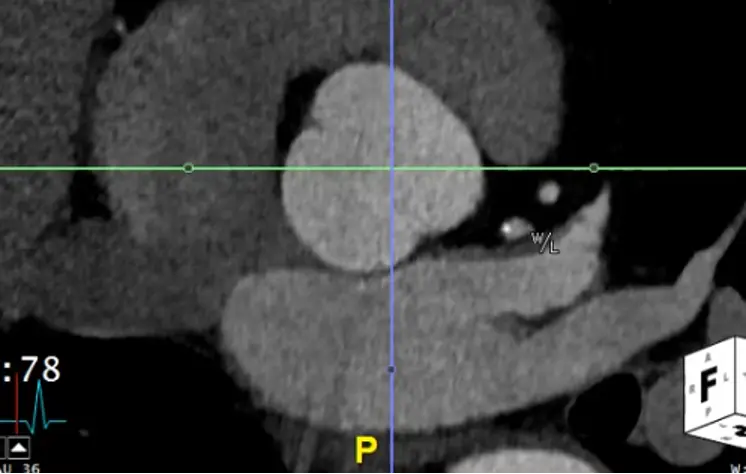

- Start at the sinuses of Valsalva

- Hit

Xto grab your cross-hairs. You will drag the cross hairs to the middle of the sinuses of Valsalva in the axial view window. - In your coronal view window, there is a pink/red line with a small circle. Drag this circle to line up the pink/red line to be perpendicular to the wall of the sinus of Valsalva. The blue/purple line should be in the center of the long-axis of the aorta at the sinus of Valsalva.

- Similarly for your sagittal view, you will want your pink/red line to be perpendicular to the sinuses of Valsalva. You will also want your green line to be in the center of the long-axis of the aorta at the sinus of Valsalva.

- Once youâve lined things up, in your axial view window you will now have what is called a âtrue short axisâ of the aorta at that level.

- Slide up and down to evaluate the AV anatomy. You will be able to determine if it is tricuspid, bicuspid, etc.

- Recall, the RCC is going to be the most anterior cusp. HINT: There is an âAâ (for anterior) at the top of the axial window and a âPâ (for posterior) at the bottom to help orient you.